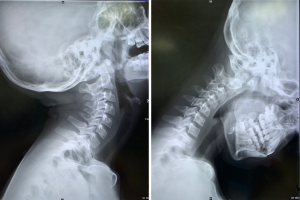

Traditionally, spondylotic myelopathy generally begins with degenerative changes in the intervertebral discs causing secondary changes in surrounding soft tissue and bony structures (8). Nevertheless, we noticed that many cases had a higher ratio of posterior atlanto-occipital interval (PAOI) (Figure 1), which was calculated by hyperextension-flexion X-ray films, and those affected were more susceptible to developing cervical spondylotic myelopathy. We hypothesized the existence of an undetected disease, and the disease could cause the development of cervical spondylotic myelopathy. Furthermore, the relationship between the interval ratio, cervical spondylotic myelopathy, and musculoskeletal dysfunction has not been examined in previous literature.

All X-ray images obtained in our institution were interpreted and diagnosed by experienced radiologists. The radiographic analysis included measuring the dynamic interval ratio and the range of motion (flexion-extension) using the following methods: (I) the interval ratio, defined as the ratio between the PAOI at the hyperflexion position and hyperextension position, as demonstrated in Figure 3; PAOI ratio = distance at hyperextension position (A'O')/distance at hyperflexion position (AO), and (II) the range of motion, which was the angle measured as the sum of 2 angles between the C2 and C7 posterior vertebral edge at flexion and extension position. The radiographic data from all cases were measured by 2 experienced, independent observers from our department twice to reduce intra- and inter-observer bias, and the mean values were determined and utilized.

A 12-year-old boy with a chief complaint of neck and shoulder pain for more than 2 years presented to our hospital. The patient was neurologically intact, and the physical examination showed a limited cervical range of motion. Although the hyperflexion-extension plain film examination showed no instability, an increase in the ratio of PAOI (PAOI = ~1) and extremely small PAOI distance were observed. In addition, the patient was found to have cervical curvature changes and mild cervical disc degeneration on MRI scans. Conservative treatment was initiated.